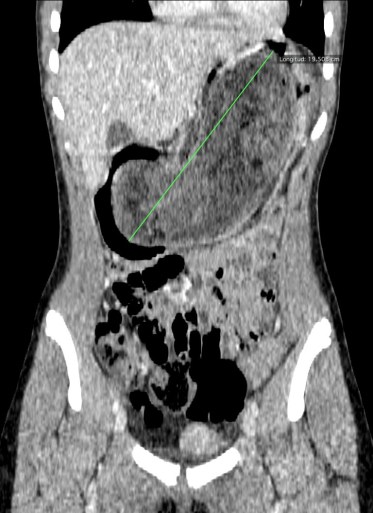

Finalmente, se realiza un TC abdominal:

Estamos ante un tricobezoar intrgástrico único. No hay obstrucción de asas intestinales.

- CT abdominal: Es la prueba de elección.

- Masa con baja densidad intraluminal + patrón de burbujas de aire moteado ( patrón característico).

- Edema de pared y engrosamiento de mucosa.

- Obstrucción intestinal: cambios de calibre y dilatación de asas pre estenosis. El CT puede determinar la causa, localización y grado de obstrucción intstinal.

- El CT puede ayudar a distinguir entre un bezoar y particulas de comida. Los bezoares son redondos u ovoides, flotan en la superficie de agua/aire rodeados del contenido gástrico y que además muestran menor densidad que las partículas de comida. Los bezoares grandes tienden a rellenar todo el lumen y muestran burbujas distribuidas en el intersticio de la masa. Sin embargo, en ocasiones puede ser dificil difrenciar un bezoar de un cantidad considerable de comida retenida o de las heces si se localizan en el colon. Un hallazgo que puede ayudarnos, es identificar que dicha masa esta produciendo una obstrucción.

- La ventana estándar abdominal de (level, 40 H; width, 350 H) puede hacer muy dificil el diagnóstico de bezoar. Es recomendable bajar el Nivel/Level de la ventana hasta los L -1oo H o jugar con dichos niveles hasta identificar mejor las características del bezoar.